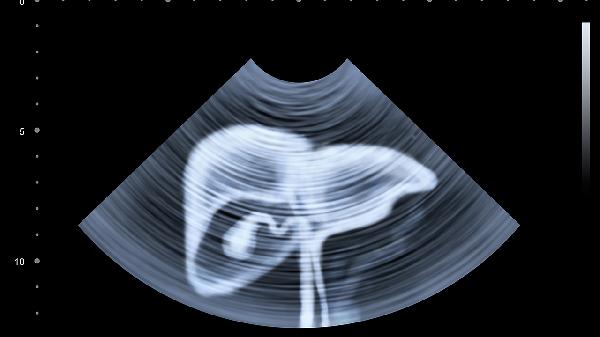

4.腹部肿胀和疼痛也可能与肝脏疾病有关。肝脏肿大或腹水会导致腹部不适。如果伴随恶心、呕吐等症状,需警惕肝脏问题。医生可能会建议影像学检查,如B超或CT,以评估肝脏形态和功能。